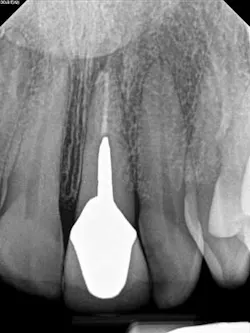

A 52-year-old male patient presented to the office with pain related to tooth No. 9. After radiographic review (figure 4), it was noted that No. 9 had previous endodontic therapy along with a large cast post. The patient was happy with the esthetics of the crown on No. 9, and the clinical and radiographic review showed intact margins and a sound restoration. The recommendation was made to take a narrow-field CBCT image of tooth No. 9. It revealed periapical pathology related to tooth No. 9 that had not broken through the buccal or palatal cortex (figure 5). No fractures were noted and disassembly of the current restoration was not ideal due to the size of the casting in place. The patient was appointed for microsurgical endodontic treatment to save tooth No. 9.

Again, a very minimal osteotomy could be made with the use of an operating microscope. After proper root resection, root-end prep, the placement of a biocompatible bioceramic filling (figure 6), the site is ready to be grafted. The lesion is removed and sent for biopsy, and we are left with a zero-degree bevel to root-end prep, and filling at this point becomes analogous to a Class I restoration. After radiographic verification that we have proper root resection and adequate apical fill, our bone grafting material was placed and final radiographs where taken (figure 7).